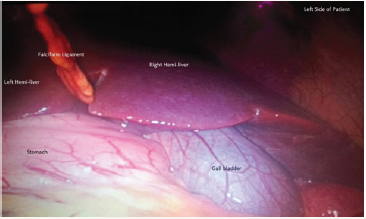

Figure 3: Image showing stomach, liver and falcifarm ligament with gall bladder on its left.

Patient was positioned in slight reverse Trendlenberg position with left up. Four port laparoscopic cholecystectomy was done with two 10 mm ports at umbilicus and epigastrium and two 5 mm ports in left midclavicular and left anterior axillary line in subcostal region (Figure 2). Pneumo-peritonium was created by open technique via umbilical port. Other ports were put under vision. Umbilical port was used as camera port. Calot’s triangle anatomy was mirror image of normal. Dissection was done through midclavicular port and epigastric port was used to manipulate the gallbladder (Figure 2-4). The right handed surgeon faced some difficulty in orientation of structures and instruments. Total operative time was 50 minutes which was about 10 minutes more than the average time for routine laparoscopic cholecystectomy by us.